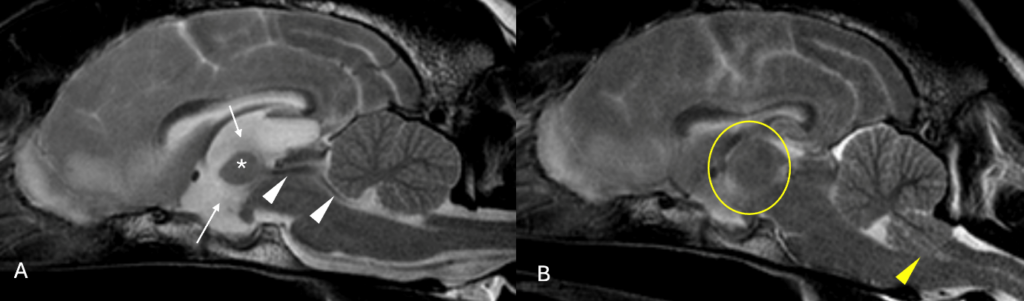

In a larger study, 0.15% of dogs experienced a major complication from over 7000 CSF collections performed in a veterinary referral practice setting. Complications included cardiopulmonary arrest or severe neurological deterioration leading to death or euthanasia. Clinical signs that were more commonly picked up in these dogs, included obtundation and multifocal neuroanatomical localisation. Changes that were observed on the MRI studies before the CSF collection, included effacement of the cerebral sulci suggesting expansion of brain parenchyma and dilatation of the ventricular system, suggesting increased intraventricular pressure. Repeat MRI after the complication could aid in understanding in the reason of deterioration (Figure 2).